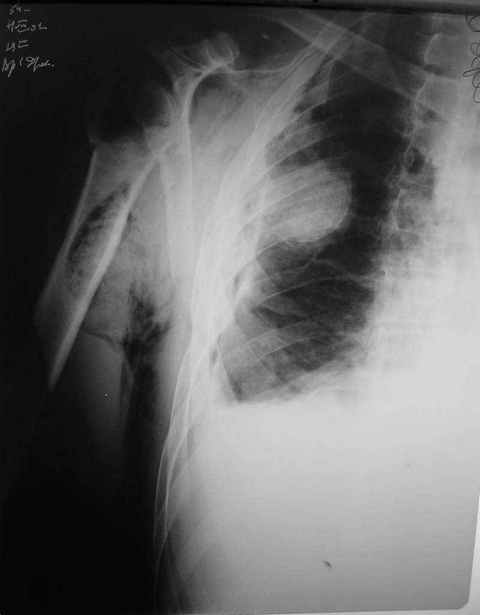

Уважаемые коллеги. Недавно из нашего отделения был выписан пациент 54 лет с закрытым переломом плечевой кости. Из анамнеза: за 2 дня до поступления в НИИСП, в состоянии алкогольного опьянения упал с лестницы на даче (высота 3-4 метра) с упором на правую руку. Через двое суток обратился за медицинской помощью. Доставлен бригадой "Скорой помощи".Правый плечевой сустав умеренно деформирован. По внутренней поверхности плеча имеется кровоподтек. При пальпации плечевого сустава имеется умеренная болезненность. Активные и пассивные движения болезненные. Снижена чувствительность по тыльной поверхности пальцев кисти и отсутствует активное разгибание кисти и пальцев. Имеется подкожная эмфизема шеи, верхней половины грудной клетки (рис 1, 2). На рентгенограмме: оскольчатый перелом головки плечевой кости со значительным смещением, перелом 2-3 ребер справа, тканевая эмфизема (рис 3). КТ при поступлении: перелом головки плечевой кости в области анатомической шейки со смещением отломка головки в грудную полость, правосторонний гидроторакс, перелом 2-3-4 ребер справа. (рис 4). Через двое суток после поступления выполнена операция: атипичная торакотомия, эвакуация свернувшегося гемоторакса, удаление инородного тела (головки плечевой кости) из плевральной полости (при этом выявлено имеющееся повреждение париетального и висцерального листков плевры) (рис. 5), дренирование плевральной полости, замещение проксимального конца плечевой кости спейсером из костного цемента с антибиотиком (рис. 6). Послеоперационный период протекал гладко. При контрольной рентгенографии положение спейсера удовлетворительное (рис. 7, 8). Дренаж из плевральной полости удален через 3 суток после вмешательства. Послеоперационная рана зажила первичным натяжением. Через 12 дней после операции больной выписан на амбулаторное лечение.

Я абсолютно согласен с Вами. Бугорки мы не выделяли и не фиксировали. Дело в том, что основная линия перелома проходит по анатомической шейке. И ниже нее кость повреждена, но существенного смещения осколков и бугорков до и во время операции не отмечено (прилагаю первичный снимок лучшего качества - рис. 1).